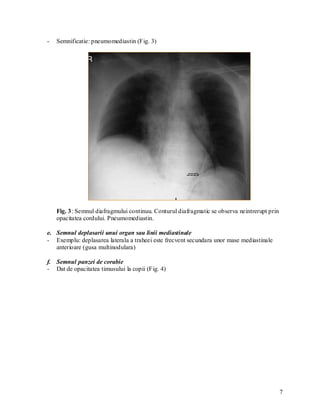

d. Semnul diafragmului continuu

- Conturul diafragmatic nu este intrerupt de opacitatea cordului

6

-   Semnificatie: pneumomediastin (Fig. 3)

Fig. 3: Semnul diafragmului continuu. Conturul diafragmatic se observa neintrerupt prin

opacitatea cordului. Pneumomediastin.